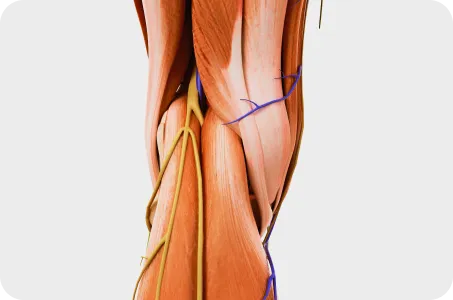

“당당은 뼈만 보지 않습니다.”

근육과 근막의 정렬을 함께 진단하며, 풀 스파인 촬영을 통해 머리부터 모든 고관절, 발의 정렬까지 함께 파악하여 개개인에 맞는 전신 치료법을 설계합니다.

속까지 볼 줄 알아야 진짜 전문가입니다.

내부 장기의 무력과 긴장, 틀어짐이 체형의 틀어짐을 유발합니다. 예를 들어, 우측에 위치한 간이 아래로 처질 경우, 우측 어깨가 따라서 처지게 됩니다. 연산당당한방병원은 대학병원급 CT, MRI 장비를 통해 내과 전문의와 협진하여 숨어있는 내장기 문제까지 진단하고 치료합니다.

모아레 근육 균형 검사

Skin rolling 근막 검사